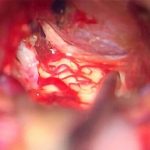

No.’22_12  摘出 中